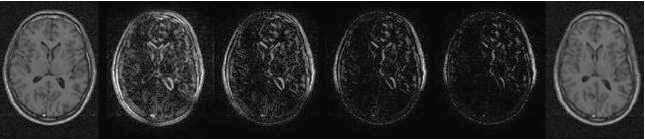

Figure: comparison between shuffle difference images evaluated using various size neighbourhoods (radius $r$). Left: original image, right: warped image, centre, from the left: shuffle difference images with $r=1$(Euclidean), $1.5,\,2.9$ and $3.7$ pixels.

Image shuffle_comparison-revised